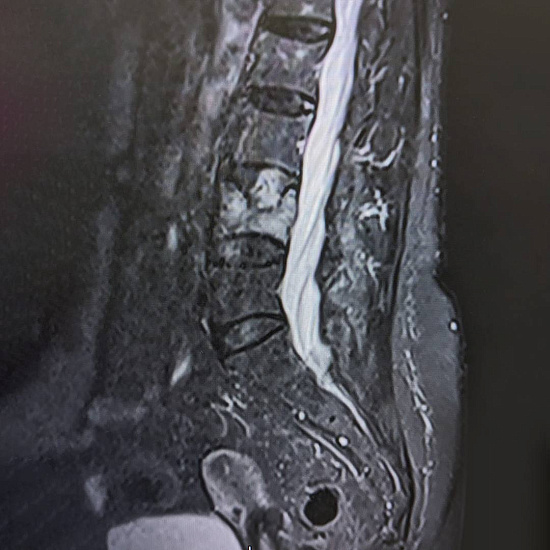

При магнитно-резонансной томографии был выявлен перелом четвертого поясничного позвонка на фоне мягкотканого образования в теле позвонка, вследствие чего пациентке было предложено выполнить дообследование в виде компьютерной томографии.

По результатам КТ и МРТ было заподозрено наличие агрессивной гемангиомы или плазмоцитомы позвонка как причины перелома.